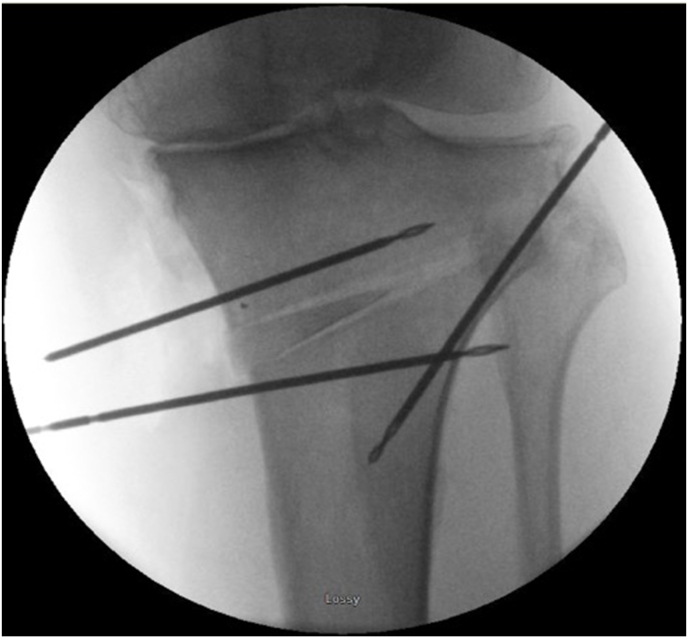

Fig. 6.

After two drill tipped wires had been positioned to either side of the osteotomy and a laminar spreader was placed between the two wires to gradually open the gap, a tailor-made allograft wedge was positioned in the gap. The ‘hinge wire’ is in-situ, protecting the hinge point.